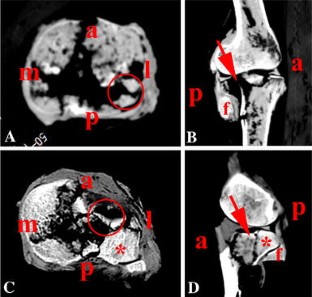

One hundred and sixty-four (44.32 %) bicondylar tibial plateau fractures finally satisfied our requirements. Fifty-three and ninety-four cases were measured eventually in the groups of posterolateral split and depression. The posterolateral articular fragment proportion was 15.43 %. The posterolateral articular fragment angle showed an average of 12.94°. The posterolateral fragment cortical height was on average 2.96 cm. The posterolateral sagittal fragment angle averaged at 72.06°. Ninety-four cases were measured in the posterolateral depression group. The average posterolateral articular depression proportion was 16.74 %. The average posterolateral articular depression height was 2.47 cm. In the biomechanical modeling of such kinds of fracture patterns, posterolateral split fractures in 30° and 60° flexion are significantly more than those in 90° flexion. Posterolateral splits combined with anterolateral depression fractures in 30° flexion are significantly more than those in 90° flexion.

The incidence of posterolateral fractures is 44.32 % in bicondylar tibial plateau fractures. The morphology of posterolateral area can be referenced for the surgeon in the future clinical work. The information is also helpful for the design of locking plate and fracture modeling in biomechanical test. In addition, that posterolateral split and posterolateral depression might be caused by different injury mechanisms. Different angles of knee flexion under the axial impact loading are possibly the interpretations for these two fracture patterns.